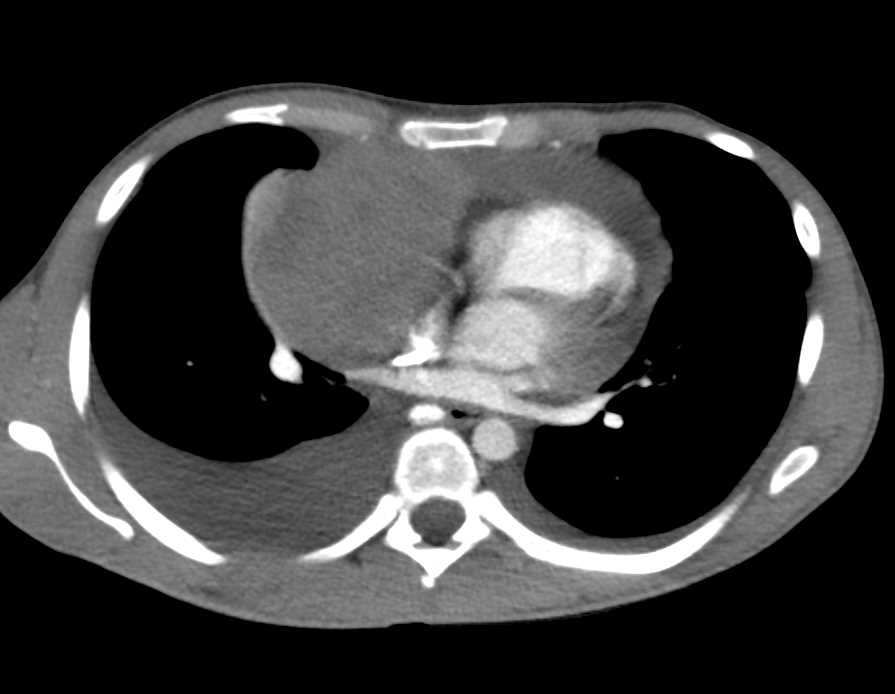

Lymphoma